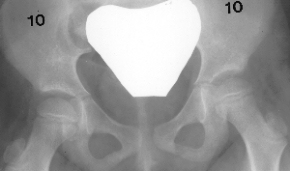

11m.. Crawling: 2y.+6m.. At 2y. + 3m., an initial X-ray showed a migration

index of the right hip of 30% and the left hip 50%.

Popliteal angle was 30 degrees bilaterally, x-ray showed normal hips.